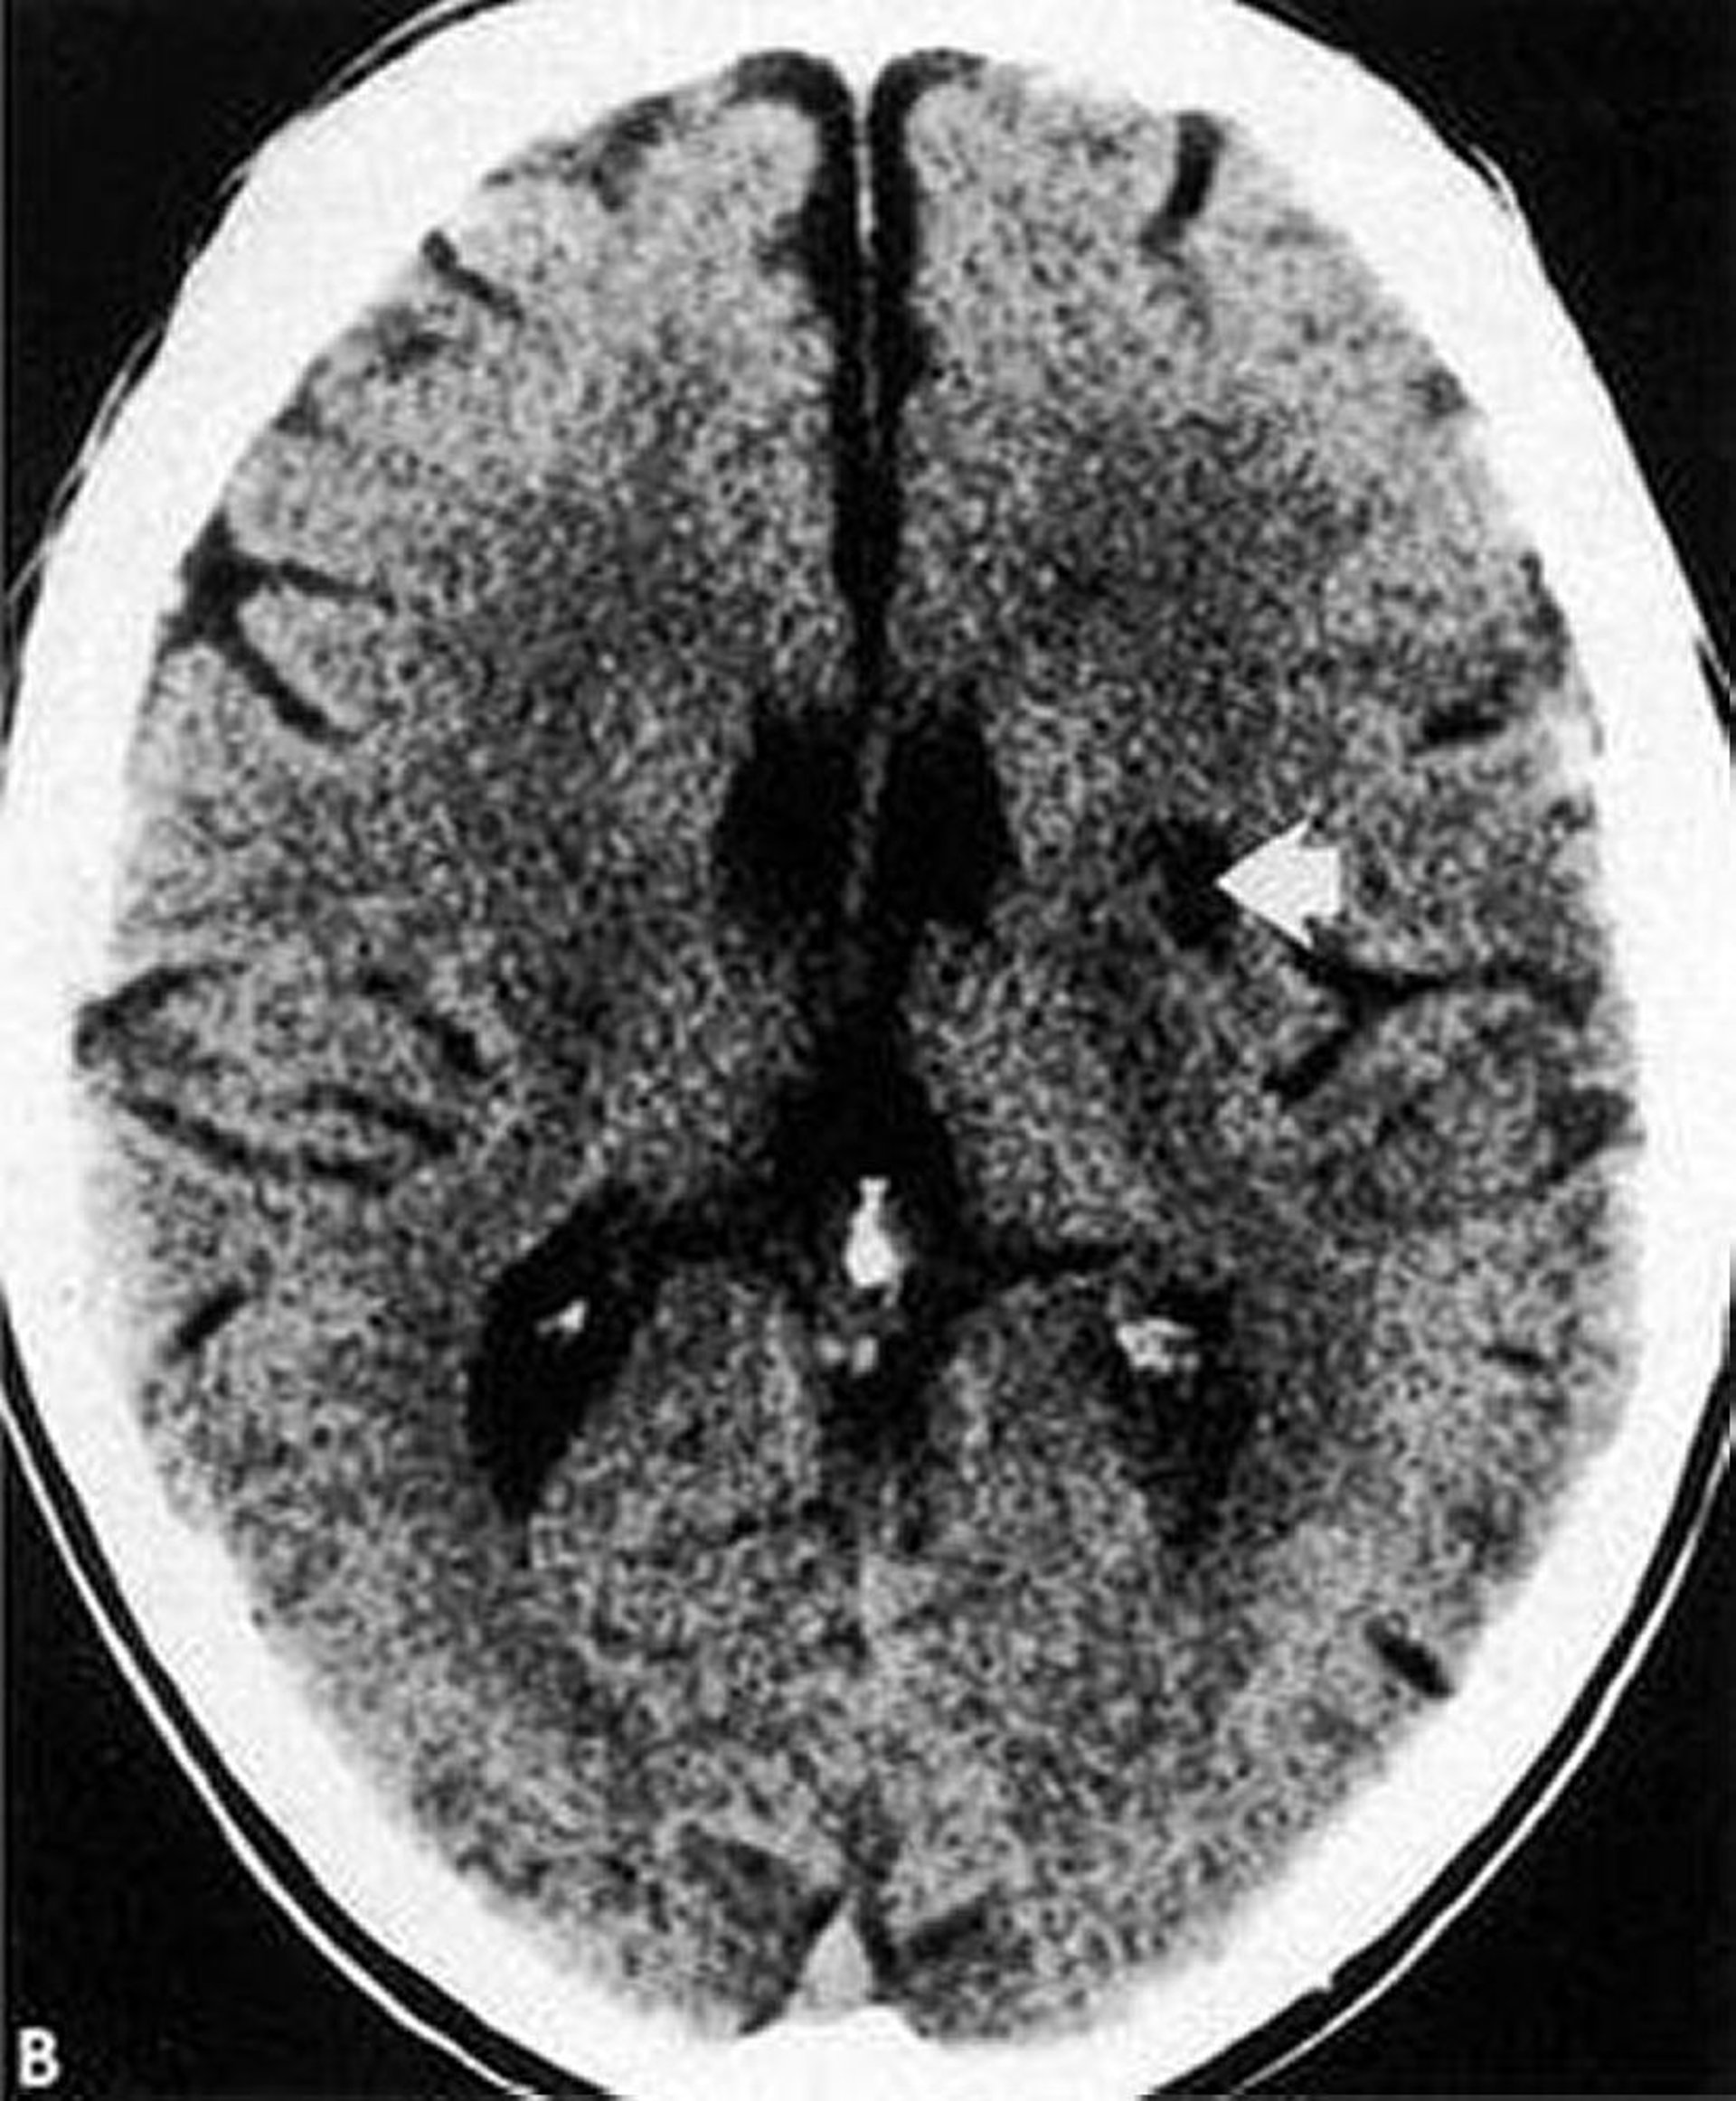

Essa TC mostra infarto lacunar de baixa densidade e bem definido (seta) nos gânglios da base.

By permission of the publisher. From Geremia G, Greenlee W. In Atlas of Cerebrovascular Disease. Edited by PB Gorelick and MA Sloan. Philadelphia, Current Medicine, 1996.